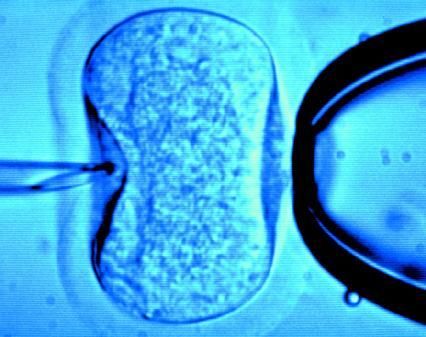

試管嬰兒是指分別將卵子與精子取出后,置于試管內使其受精(資料圖)